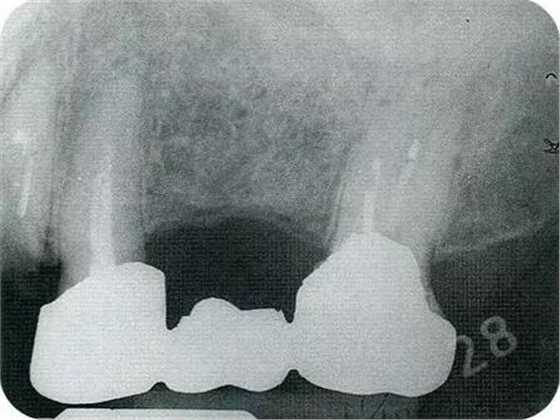

▼圖16-1 ▼圖16-2

圖16-1對(duì)右上6.7分叉部病變處理時(shí),對(duì)包括右上4.5進(jìn)行齦瓣分割,確認(rèn)骨缺失狀態(tài)。右上7頰側(cè)存在著12mm的骨緣下缺失。

圖16-2右上6水平的分叉部病變到達(dá)了III度。